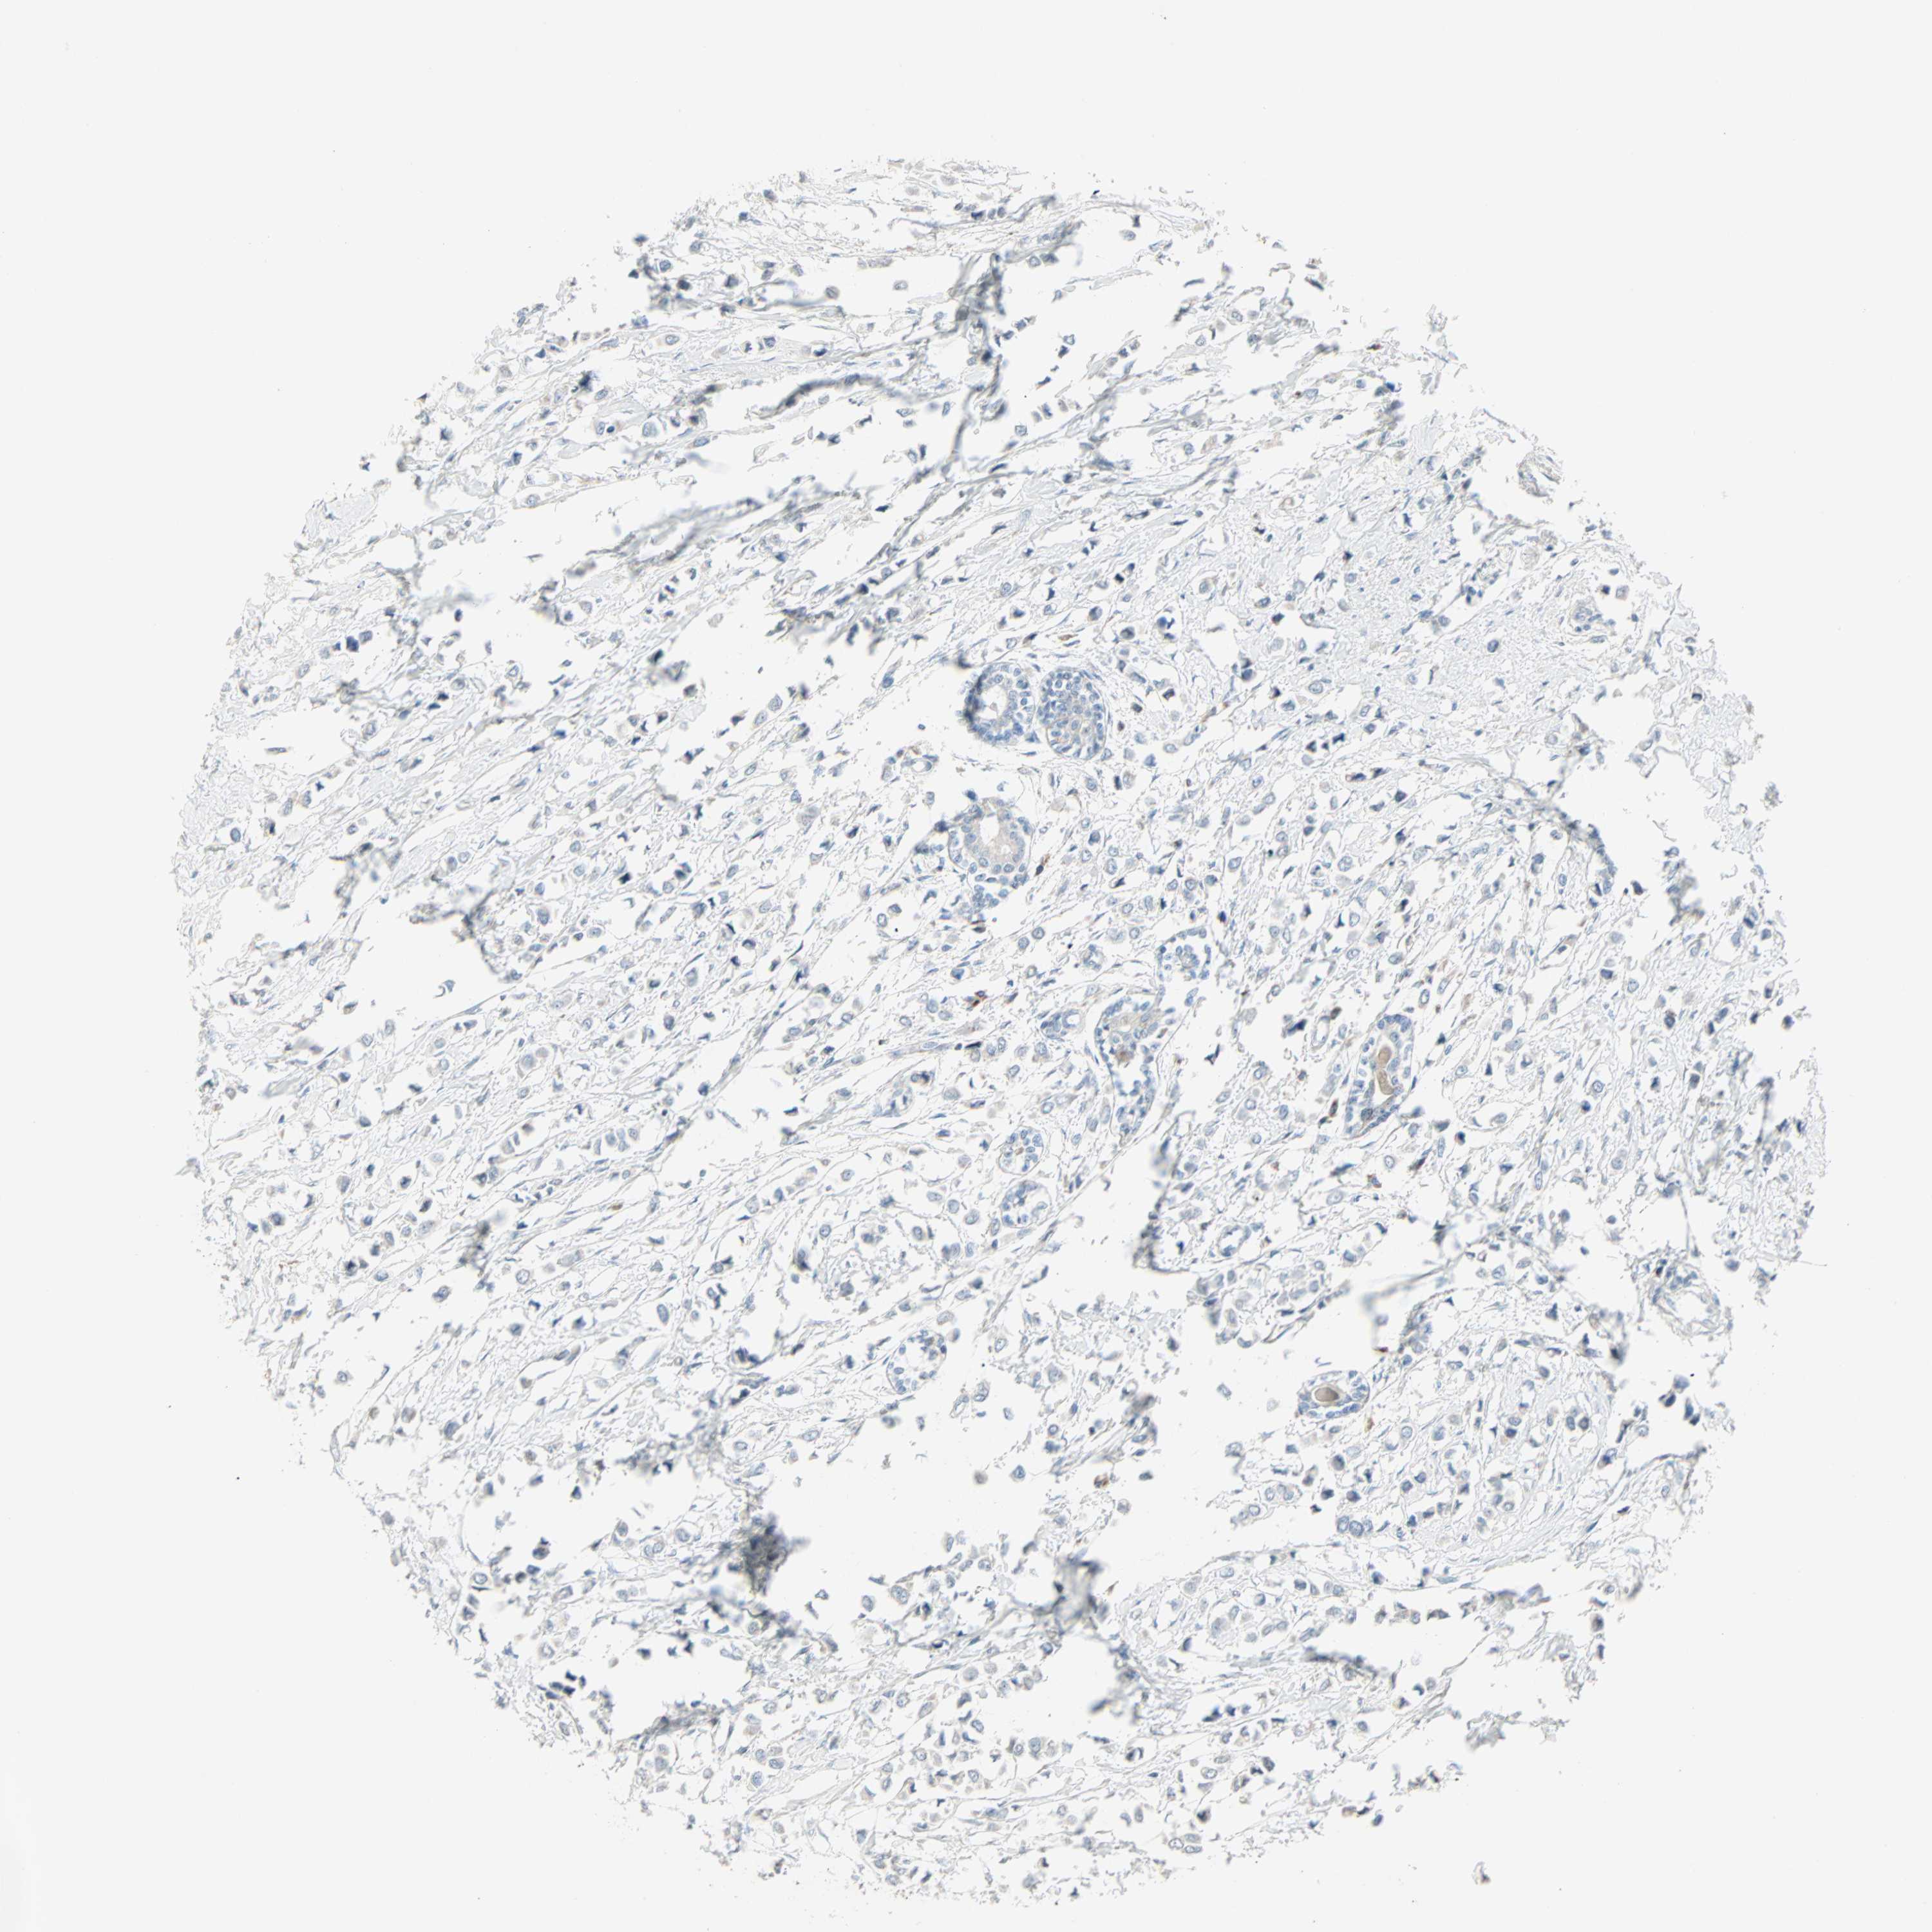

CANCER BREAST CANCER Show tissue menu

BRCA TCGA BRCA VALIDATION PROTEIN EXPRESSION

Breast cancer

Human cancer